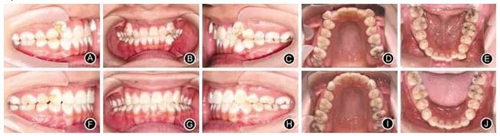

例2:患者女,18歲,要求排齊牙列,并在1年內(nèi)完成治療。臨床檢查,雙側(cè)磨牙輕度遠(yuǎn)中關(guān)系,上牙列重度擁擠,下牙列中度擁擠,前牙Bolton比為78.12%,直面型,低角。正畸設(shè)計(jì)減數(shù)上頜兩顆第一前磨牙和左下中切牙,全口固定矯治,治療過(guò)程中調(diào)磨左下尖牙牙尖解除咬合創(chuàng)傷。固定矯治時(shí)間13個(gè)月,Hawley保持器保持,其間做牙齒美白時(shí)夜間戴用透明保持器(圖3)。

圖3典型病例2

A.治療前右側(cè)位牙合像 B.治療前正位牙合像

C.治療前左側(cè)位牙合像 D.治療前上頜口內(nèi)像

E.治療前下頜口內(nèi)像 F.治療后右側(cè)位牙合像

G.治療后正位牙合像 H.治療后左側(cè)位牙合像

I.治療后上頜口內(nèi)像 J.治療后下頜口內(nèi)像